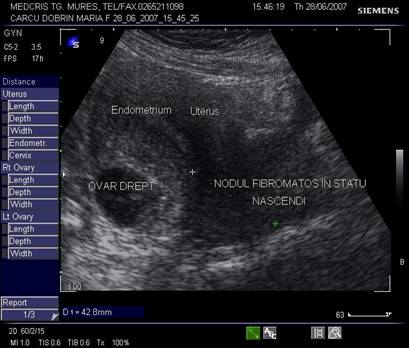

Fig, nr.380. Nodul fibromatos intramural si subseros al peretelui anterior uterin, in sectiunea sagitala a ecografiei abdominale

Fig. nr. 381.Nodul fibromatos ce prolabeaza prin canalul cervical, la ecografia abdominala